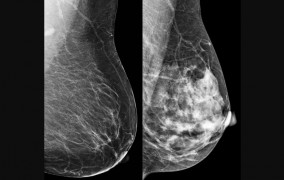

Simple quantum-classical neural networks achieve good results in classifying lesions with fewer computational parameters. Scientists from São Paulo State University demonstrated a hybrid model at an international symposium.